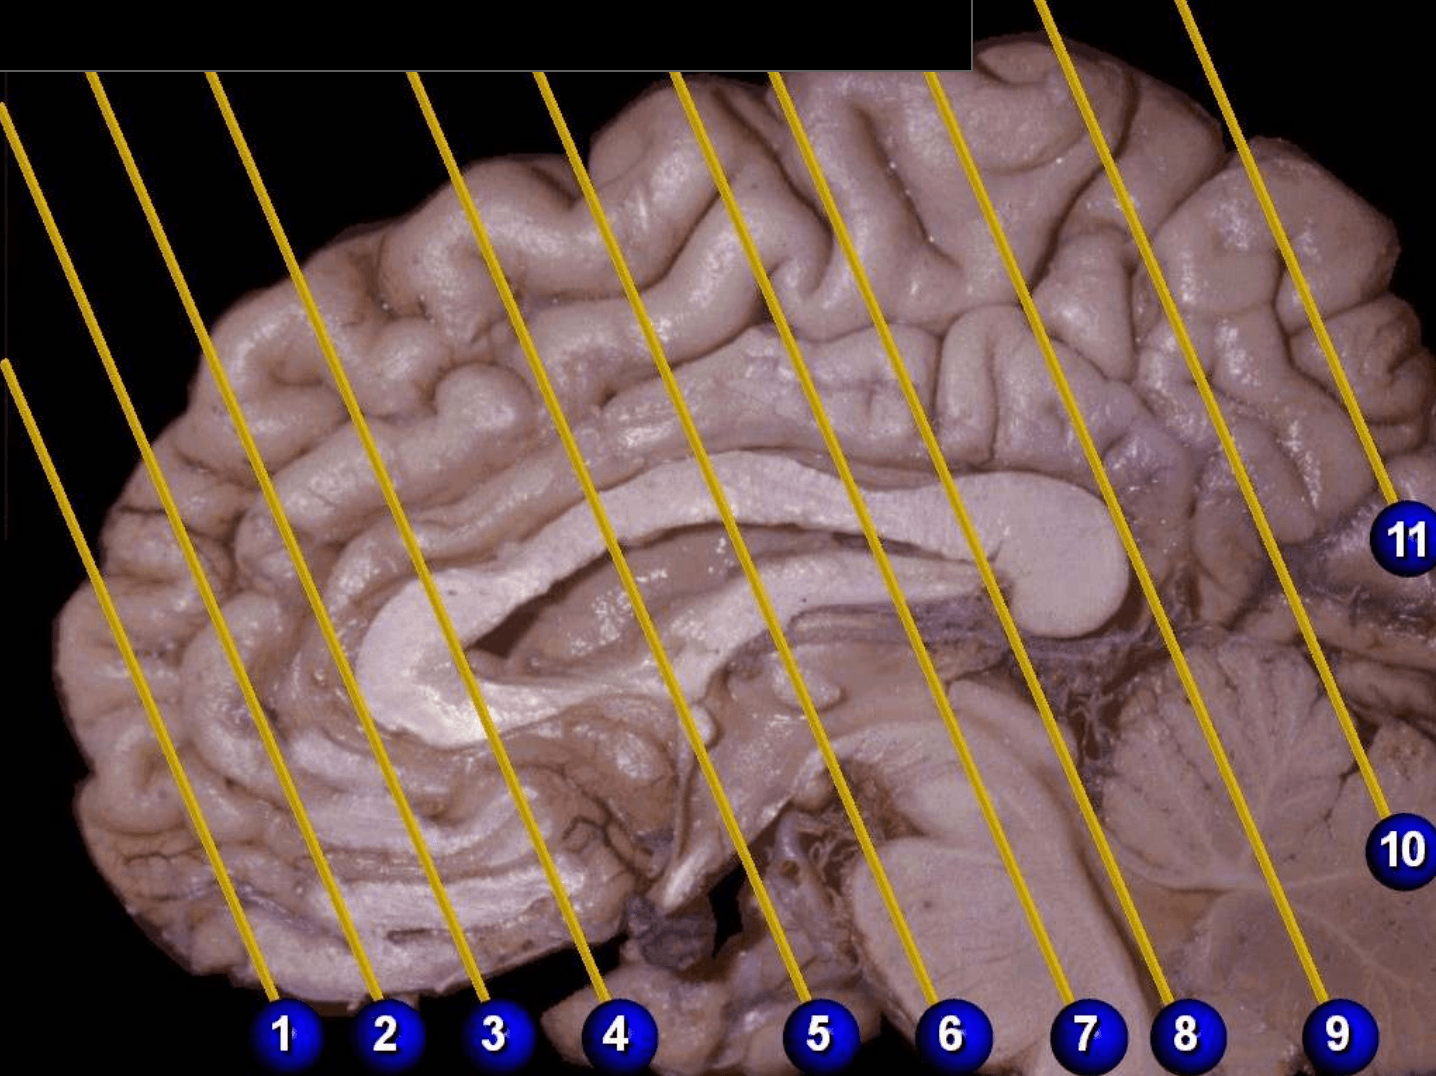

Ubicación de los cortes coronales de Jakob

Ubicación de los cortes coronales de Jakob